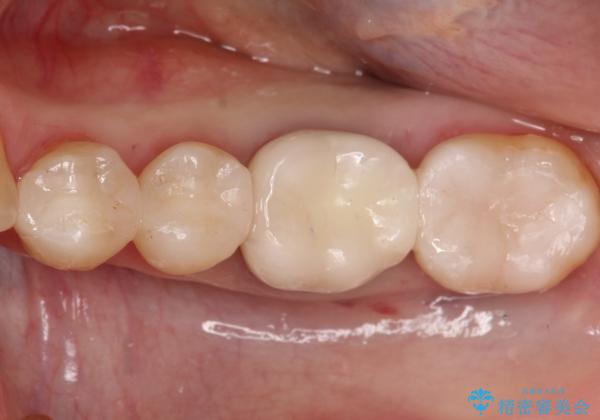

- 金属を外して白い歯を手に入れたいとのことで来院されました。

まとめて治療することで通院回数を減らすことができ、見た目も大変満足していただきました。